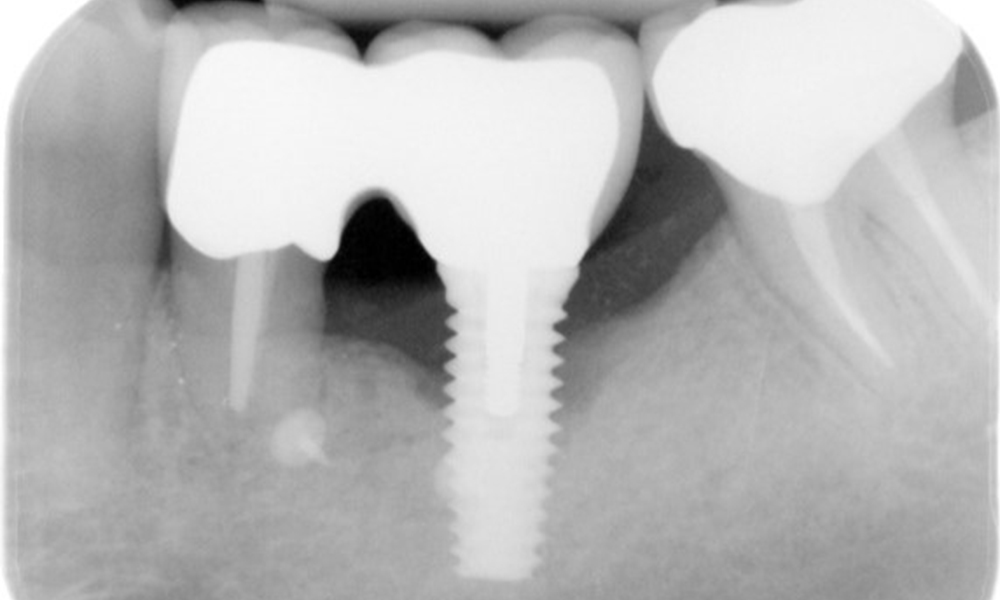

A 52-year-old patient presents at a preventive care session. The patient has no systemic disease and is not taking any medication. He has had various dental treatments and also has two active carious lesions. In addition, the patient has four implants (2nd, 3rd and 4th quadrants). He is revealed to have early periodontal disease (stage IV, grade B). His periodontal condition is stable; a probing depth of Probing depths (ST) of 5 mm is only evident at the implant in region 36. Gingivitis is also identified.

The patient has no particular risk factors with specific dental implications in his medical history. The key factor, therefore, is the requirement in terms of oral health. In this respect, there is evidence of a probing depth of 5 mm at the implant in the 3rd quadrant and, on the X-ray image, increased bone loss. The patient also has currently stable early periodontal disease and two active initial carious lesions.

In terms of instruments, specific procedures are required for use with implants. In order to preserve the surface of the implant while cleaning it effectively, it is essential to choose suitable powders and instruments, such as the targeted use of air polishing devices with special periodontal tips. Which powder is most suitable can be determined according to the needs and risk. For example, in addition to the appropriate degree of abrasion, dietary requirements (including sugar-free, low-salt) may also be taken into account.